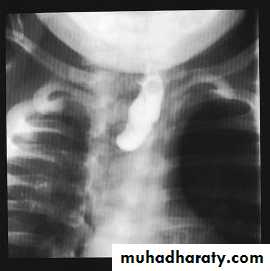

Esophageal Atresia + / ـــTracheoesophageal Fistula

Presentation :-Polyhydraminous.Frothy secretion.Respiratory distress.Resistance to NG tube insertion.Plain X-ray.

Initial management :-Suctioning.Positioning.Vascular line.Endotracheal intubation.Incubator , warm , humidity.Check for associated anomalies.Referral to pediatric surgical center.

Operative management :-Pre-op. Echo study.Intra-op. Esophagoscopy.Intra-op. Bronchoscopy.thoracotomy.